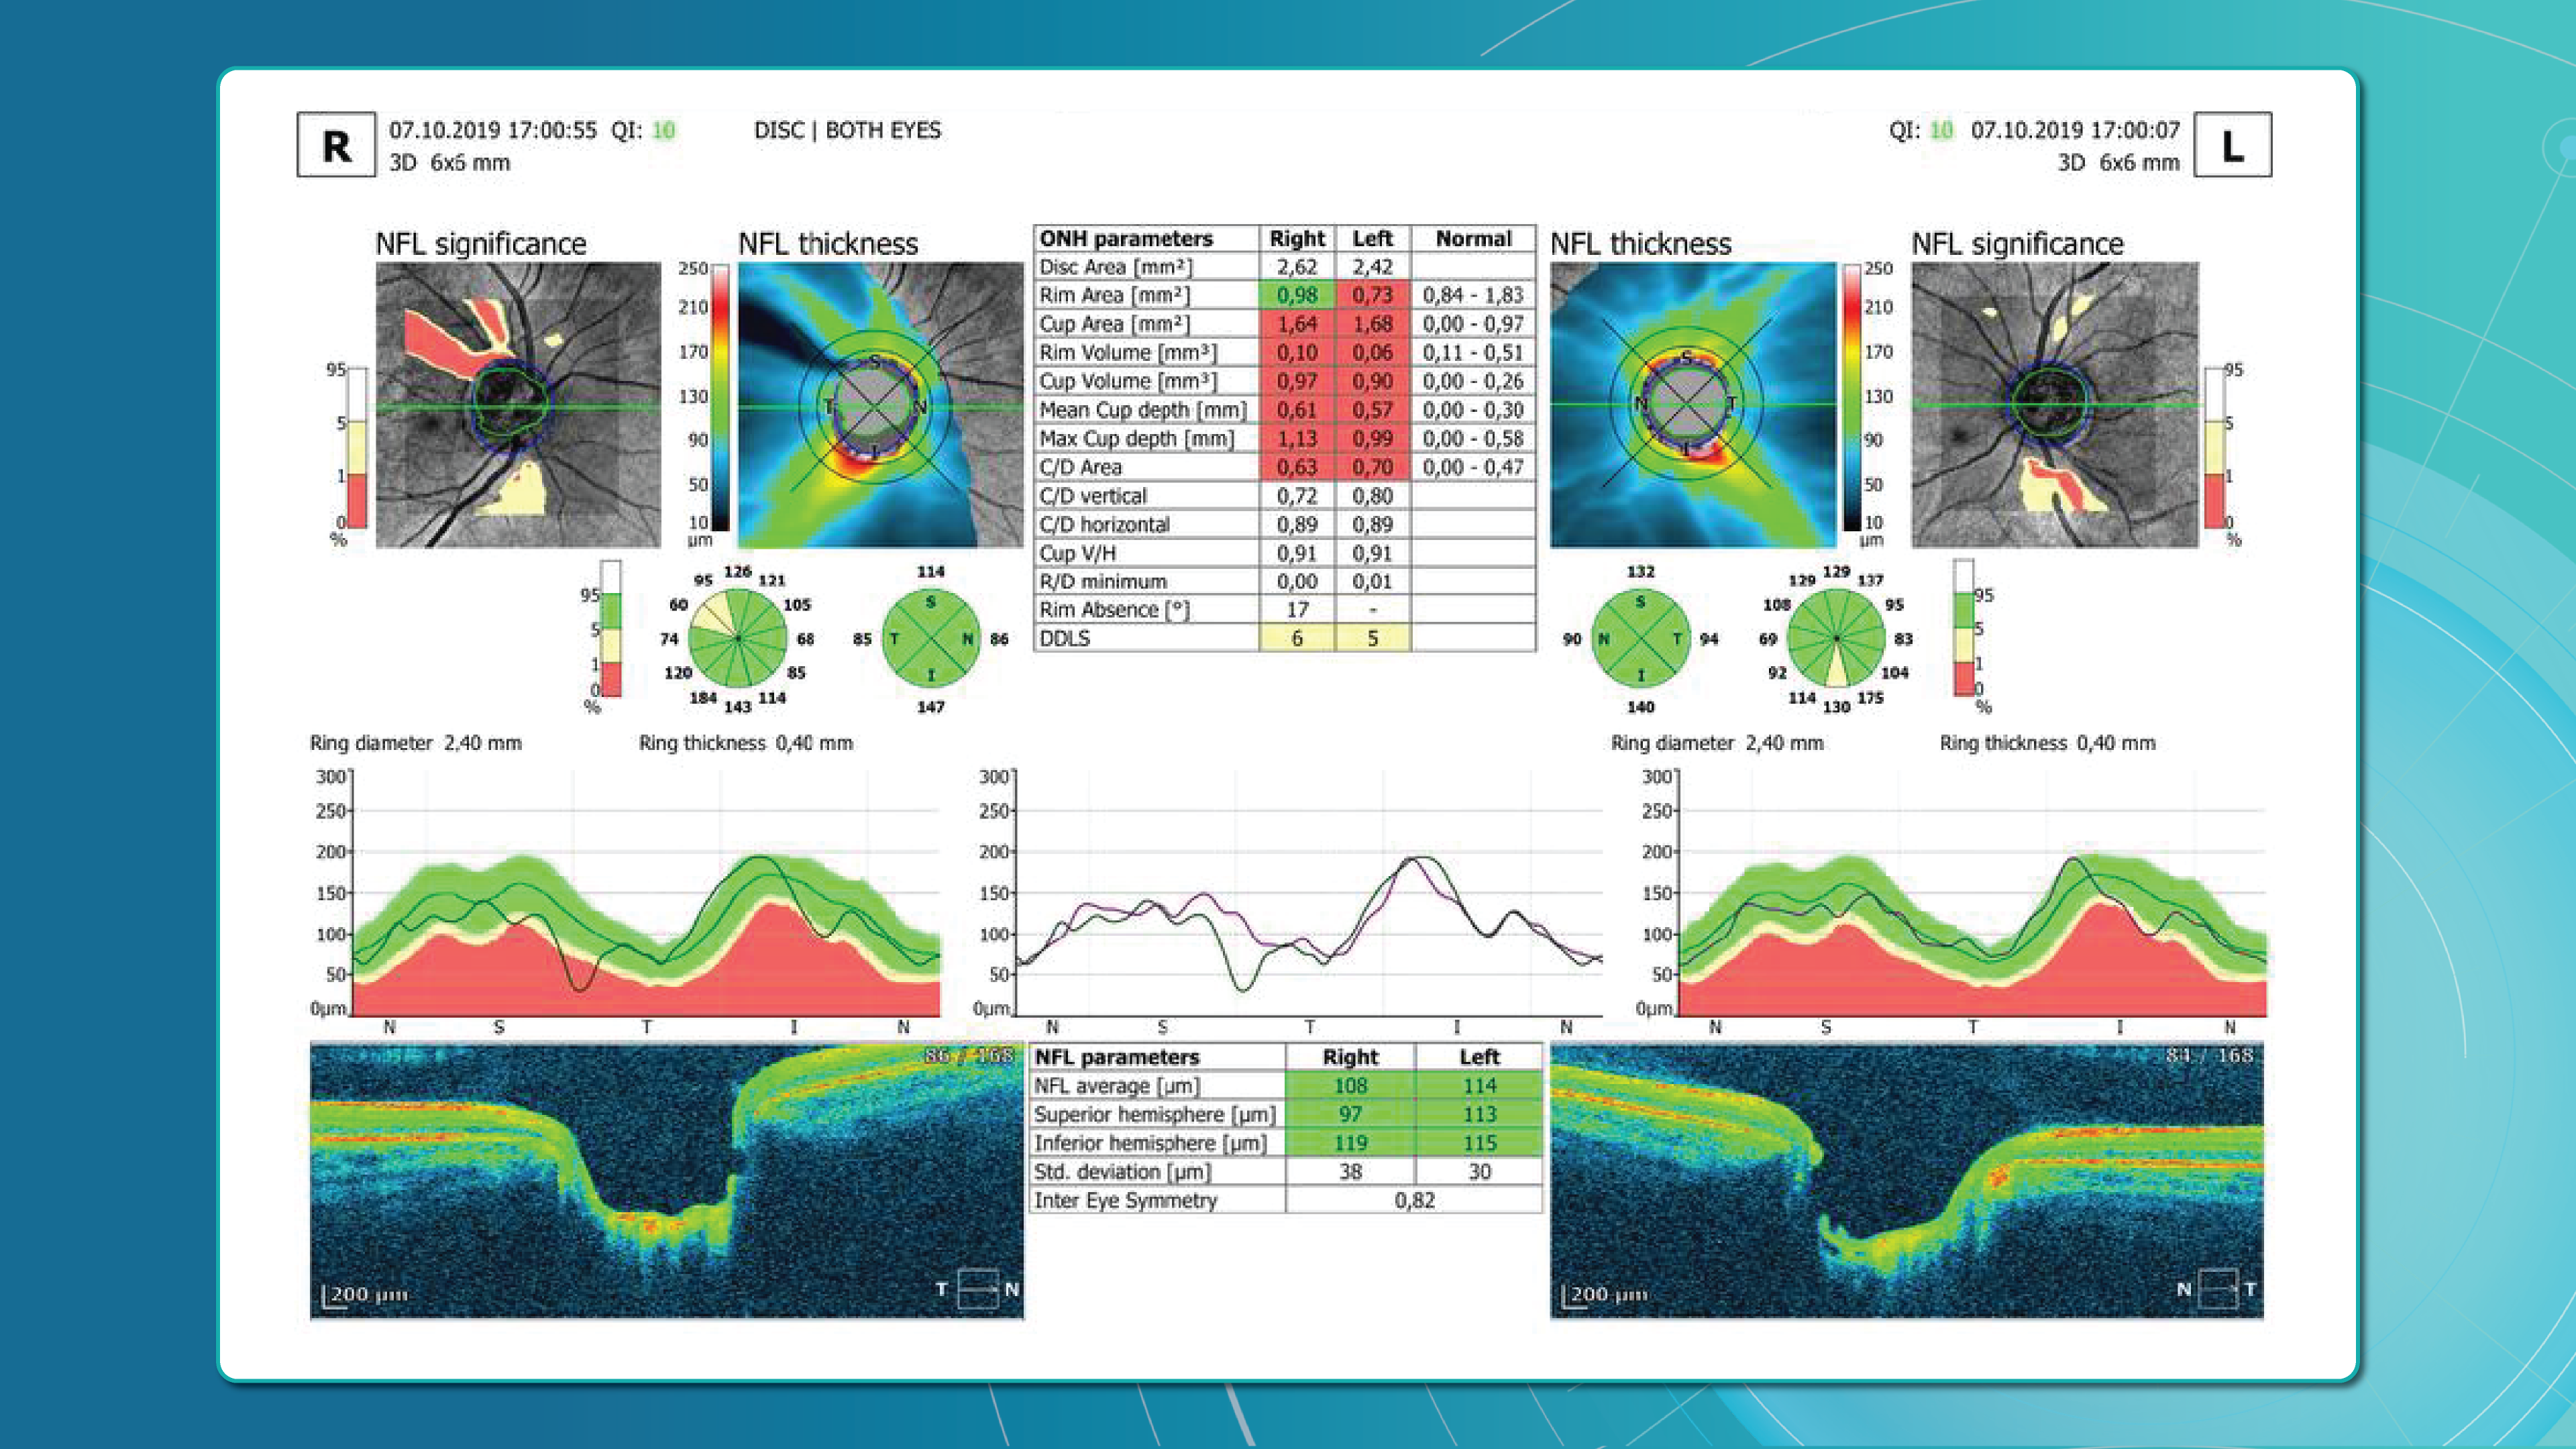

Dr. Maria Sampalis, OD, the owner of Sampalis Eye Care, Rhode Island, utilizes two such programs in her practice. To support her specialization in dry eye management, she employs CSI Dry Eye. Additionally, she uses Altris AI, an AI-powered platform for OCT scan analysis, to provide a second opinion and enhance diagnostic accuracy.

Her patients also appreciate Altris AI, which analyzes OCT scans for over 70 pathologies and biomarkers while also calculating the risk of developing glaucoma.

Eye Place, an optometry center in Columbia, also leverages Altris AI, among other cutting-edge technologies. They capture images using the Topcon Maestro2 OCT and use Image Net6 software to export DICOM files to the Altris AI platform.

Beyond AI-powered OCT analysis, Eye Place utilizes state-of-the-art diagnostic tools, such as 3D OCT equipment, to screen for serious conditions, including glaucoma, diabetes, and macular degeneration. Furthermore, they work with AdaptDX Pro, a technology capable of detecting macular degeneration earlier than traditional methods.

For instance, AI today can assess the early risk of glaucoma based on the GCC asymmetry measurements. Here is how AI-powered OCT workflow would look.

AI-assisted readings of OCT scans are already helping not only with pathology detection but also with the analysis of its progression or response to treatment. This represents a new approach to monitoring, where practitioners no longer need to sift through various patient notes but can directly compare reports from previous examinations and observe how, for instance, shadowing has changed in micrometers.

Millions risk irreversible vision loss due to undiagnosed glaucoma, underscoring the need for improved early detection. Current tests often rely on observing changes over time, delaying treatment assessment and hindering early identification of rapid disease progression. OCT frequently detects microscopic damage to ganglion cells and thinning across these layers before changes are noticeable through other tests. However, the earliest signs on the scan can still be invisible to the human eye.

AI algorithms offer insights into glaucoma detection by routinely analyzing the ganglion cell complex, measuring its thickness, and identifying any thinning or asymmetry to determine a patient’s glaucoma risk without additional clinician effort.

Another significant benefit of AI systems is that OCT for glaucoma usually utilizes a normative database to assess retinal normality. However, these databases are limited in size and represent an average of a select group of people, potentially missing early glaucoma development in those who deviate from the “norm.” Conversely, individuals may be unnecessarily referred for treatment due to not fitting the “normal” profile, even if their eyes are healthy.